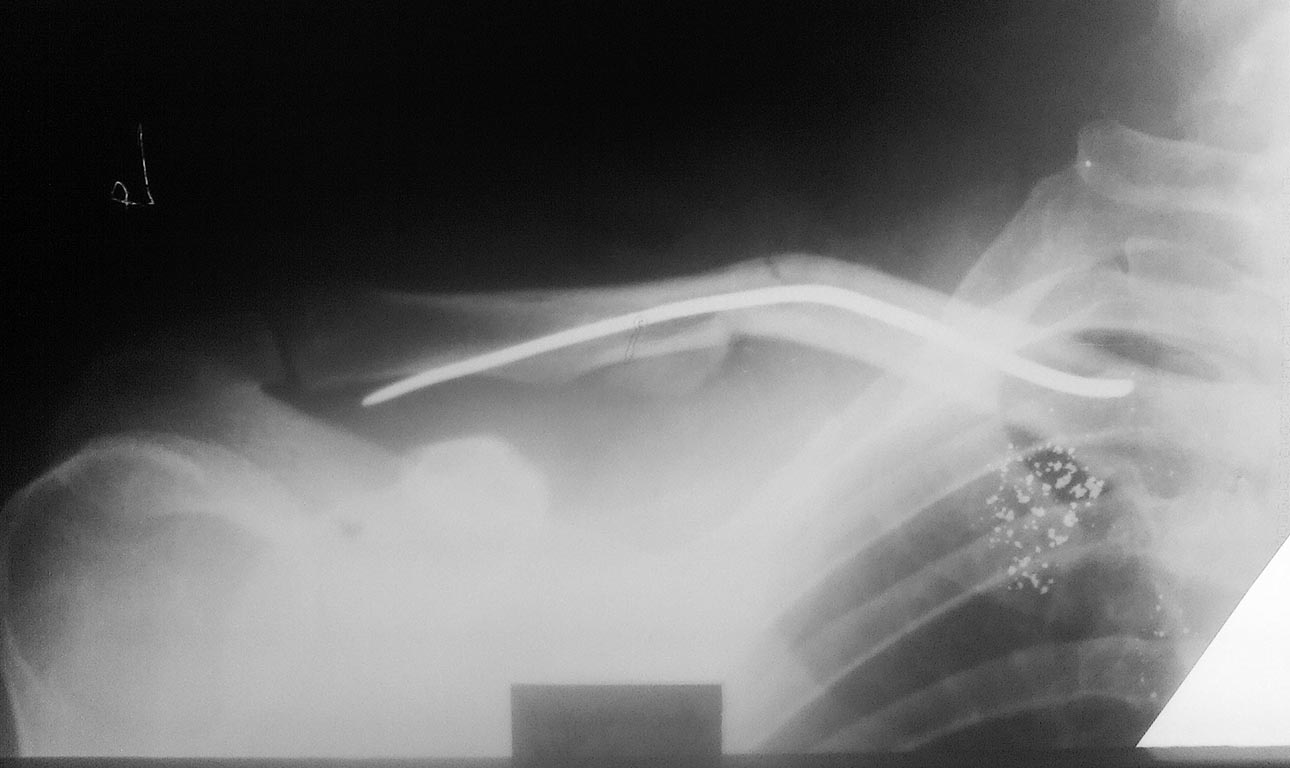

Мужчина, 35 лет, 23.11.15 получил закрытый оскольчатый перелом левой

ключицы в результате падения на руку с высоты роста. 26.11.15 выполнена

операция: Открытая репозиция, интрамедуллярный остеосинтез штифтом

Богданова, промежуточные осколки фиксированы на место лавсановыми

нитями. Остеосинтез выполнил по классической методике: через доступ

длинной 5 см экономно скелетировал отломки, рассверлил сверлом 3.2 мм

каналы в дистальном и проксимальном отломках, подобрал соответствующего

диаметра стержень Богданова, который антеградно ввбил в репонированные

отломки,промежуточные осколки фиксировал лигатурами к месту перелома.

Смущает одно, что изначально стержень не изгибал под S-образную кривизну

ключицы, а на R-графии после остеосинтеза стержень деформировался под

изгиб ключицы.

Изначально планировал стержень расположить "широкой" частью фронтально,

но не вышло.